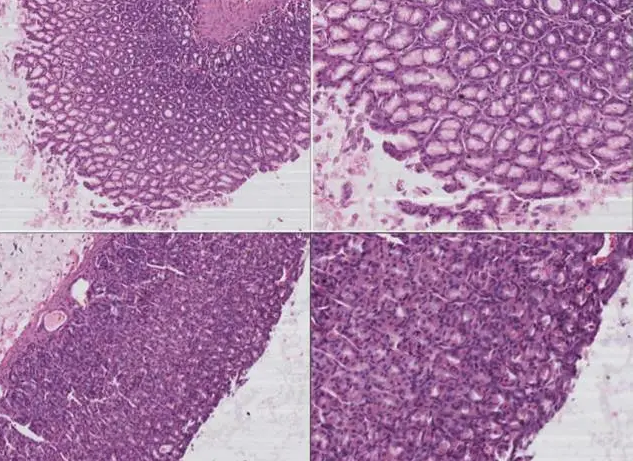

来自西安交通大学,论文发表在国际胃肠学杂志上的研究发现:氢水能保护阿司匹林诱导的胃溃疡,该效应可能和减少炎症反应,降低氧化损伤有关系。(ZhangJY, Wu QF, Wan Y, Song SD, Xu J, Xu XS, Chang HL, Tai MH, Dong YF, Liu C. Protectiverole of hydrogen-rich water on aspirin-induced gastric mucosal damage in rats. WorldJ Gastroenterol. 2014 Feb 14;20(6):1614-22. doi: 10.3748/wjg.v20.i6.1614.)

图中第三张是实验组,第四是氢水治疗,比较两者差别,效果自现

来自清华大学环境学院的一项研究也证明了电解水中氢气抗氧化是发挥治疗胃溃疡的主要原因,抗氧化效应与氢气剂量大小有关系。